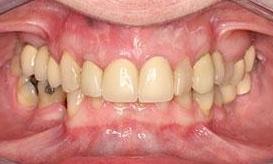

This before and after showcases a comprehensive dental restoration involving root canal therapy, the placement of dental crowns for structural integrity and aesthetics, as well as a full upper denture to restore function and appearance.